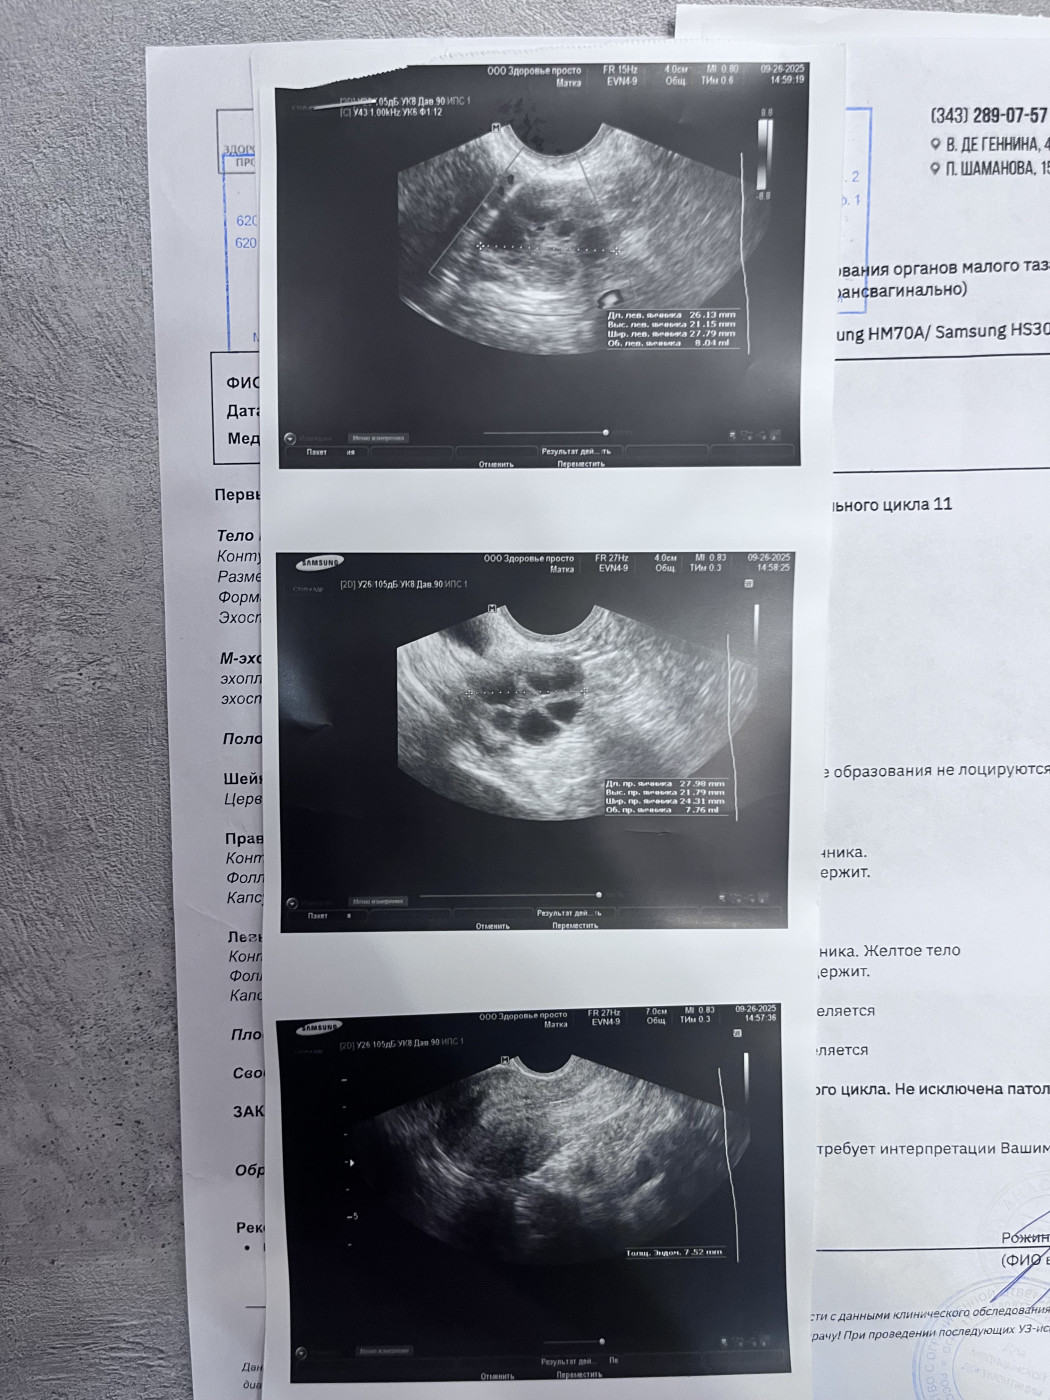

После менструального цикла назначили повторное узи, чтобы убедиться полип ли это. Также делала узи через месяц, 11 дней цикла. |

Также посмотрите снимки год назад, там все было хорошо. Спасибо Вам большое заранее |